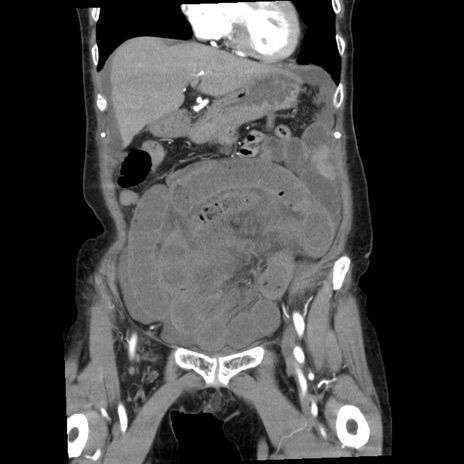

横断像

矢状断像